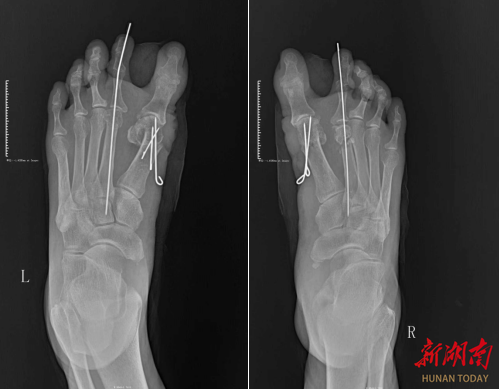

术前影像图。

手术中,周文进带领手术团队创新采用“三步复位法”:以“理线头”手法松解第二趾对第一趾的骑跨粘连,似拆解打结绳结般解除压迫;用“排好队”思路调整脚趾序列,让错位脚趾回归正常解剖位置;借“调平衡”技术矫正第一趾畸形,如校准天平般恢复足部受力平衡,实现脚趾“各安其位”。术后首日,王女士即可下床行走,康复效果远超预期。目前,患者已顺利出院。